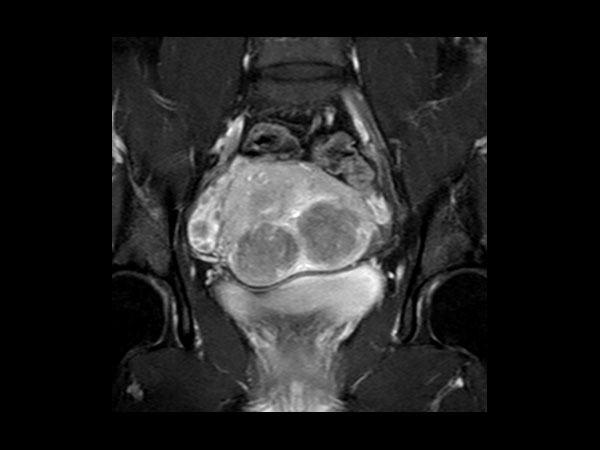

Female Pelvis

Toyonaka Hospital, Japan